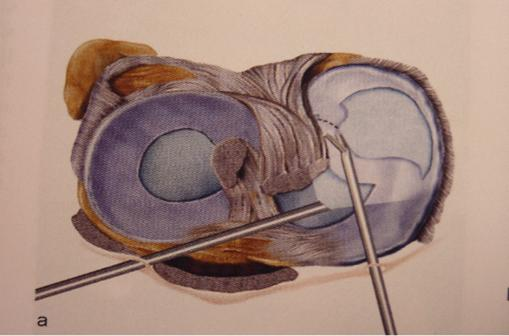

- Les lésions isolées (sur genou stable), siègent le plus souvent sur le bord libre du ménisque. Il s'agit de fissures verticales, radiaires, qui ne cicatrisent pas et qui peuvent détacher un fragment plus ou moins étendu (languette, anse de seau), source de blocage. Ces lésions doivent être réséquées par méniscectomie partielle.

Figure 2 : résection à l'aide d'une pince coupante d’une lésion en anse de seau du ménisque interne en vue de haut et en vue arthroscopique